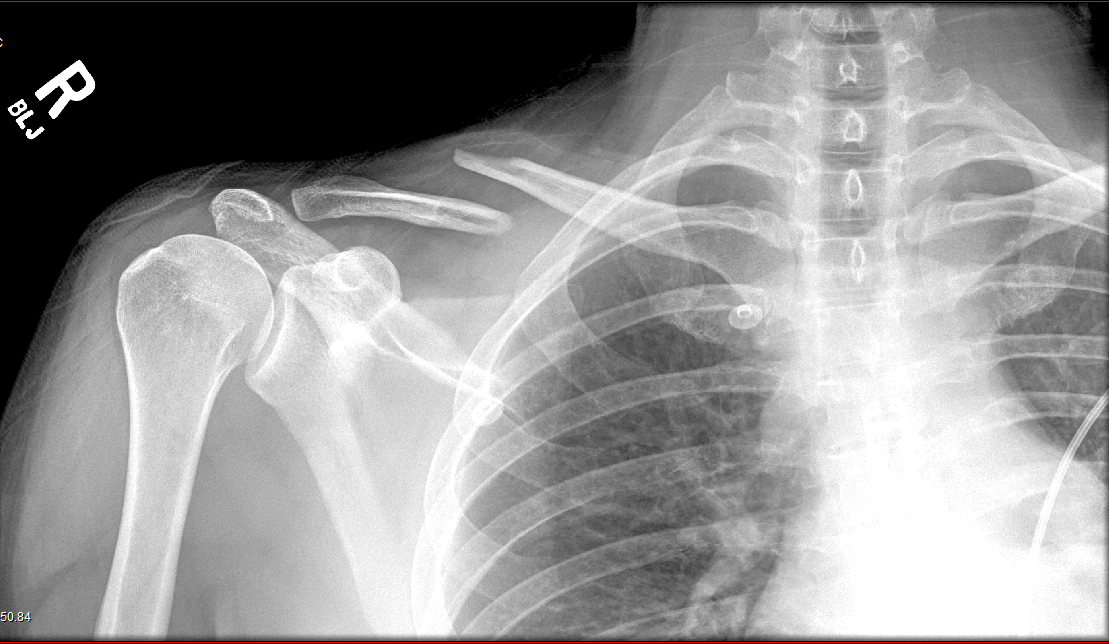

Radiography

(X-Rays)

- Uses ionizing radiation

How does it work?

- X-ray beam passed through the body

- Portion of the beam is scattered or absorbed by bones, organs, etc.

- Remaining pattern is transmitted to a detector for further processing as a picture

- Useful for detecting bone problems, infection, and tumors